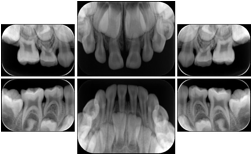

Intra-oral radiography typically involves acquisition of multiple images of various parts of the dentition. Many digital radiographic systems offer customized templates that are used for displaying the images in a study on the screen. These templates may also be referred to as mounts or view sets. The Structured Display Object represents a standard method of encoding and exchanging the layout and intended display of Structured Displays. A structured display object created in this manner could be stored with a study and exchanged with images to allow for complete reproduction of the original exam.

3. A dental provider wishes to capture a series of DICOM IO images for the patient’s dentition. The tooth morphology, teeth are divided into molars, premolars, canines and incisors, and a number of images for each jaw. The anatomic information was captured utilizing the triplet of schema. This standard code sequence is based on ISO 3950-2010, Dentistry - Designation system for teeth and areas of the oral cavity.

In most standard cases, images are oriented in structured layouts. These structured displays are useful to be shared between providers for reference purposes.